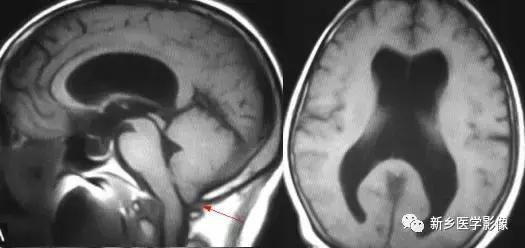

8.胼胝体发育不良

在脑发育腹侧诱导晚期,新形成的端脑嘴侧壁的背侧部分增厚、内陷,向后沿尚未完全发育的大脑半球间裂延伸。两个月后形成一个连合即胼胝体纤维的细胞框架,该细胞框架形成后胼胝体相应部分立即发育。膝部先发育。然后是体部、压部.位于胼胝体膝部后下方的胼胝体嘴最后发育。如果胼胝体发育过程中出现有害因素,就有可能导致胼胝体发育不良.表现为完全缺如或部分缺失。常表现为膝部存在或膝部和体部存在。压部和胼胝体嘴缺失。

胼胝体发育不良可见单独发病,但更常见的是伴有中枢伸经系统的其他畸形,包括胼胝体周围脂肪瘤、脑膨出、交通性脑积水Chaiarii畸形、Dandy-Walker囊肿、脑裂畸形等。临床上可无症状或仅有轻度临床症状,临床检查可见眼距过宽、大头畸形、智力发育迟滞等。胼胝体缺失时,MR冠状位上侧脑室前角呈新月形表现,侧脑室体部分离,呈垂直状平行走行。